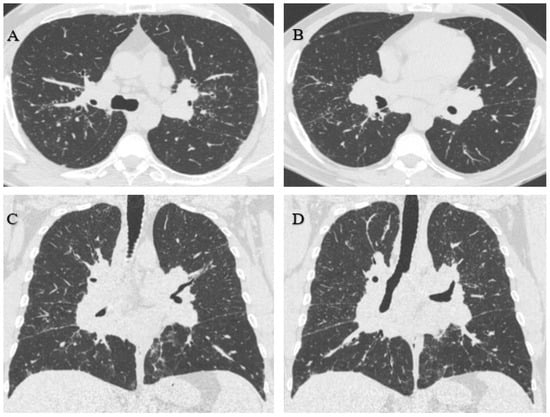

3.1.1. Case 1

3.1.2. Case 2